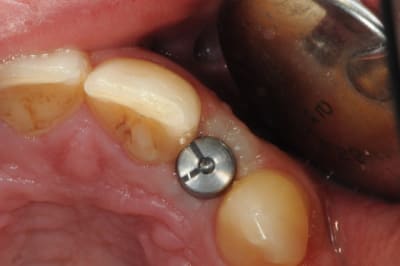

je reviens sur ce cas que j'ai un peu délaissé...

-cicatrisation

-mise en place vis de cica petit diamètre

-ensuite on augmente le diamètre en conservant et en gonflant les tissus gingivaux